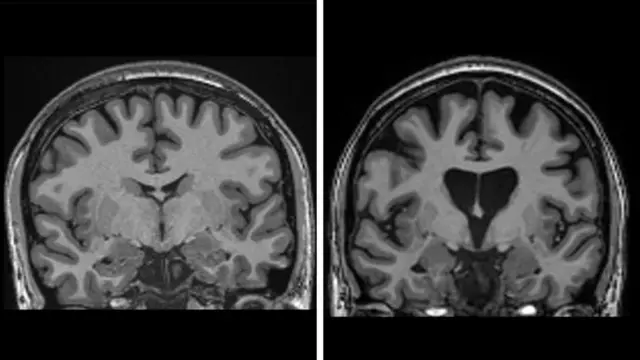

يُحقن هذا الفيروس عميقاً في الدماغ باستخدام التصوير بالرنين المغناطيسي في الوقت الفعلي لتوجيه قسطرة دقيقة "ميكروكاتيتر" إلى منطقتين في الدماغ هما النواة المذنبة واللوزة المخية. وتستغرق هذه الجراحة العصبية بين 12 و18 ساعة.

وأظهرت البيانات أنه بعد ثلاث سنوات من الجراحة، كان هناك تباطؤ بنسبة 75 في المئة في المرض بناءً على مقياس يجمع بين الإدراك والوظائف الحركية والقدرة على إدارة شؤون الحياة اليومية.

كما أظهرت البيانات أن العلاج يحمي الخلايا العصبية. فمستويات "الخيوط العصبية" في السائل الشوكي - وهو مؤشر واضح على موت الخلايا العصبية - كان يُفترض أن ترتفع بمقدار الثلث إذا استمر المرض في التقدم، لكنها كانت أقل من مستوياتها عند بدء التجربة.